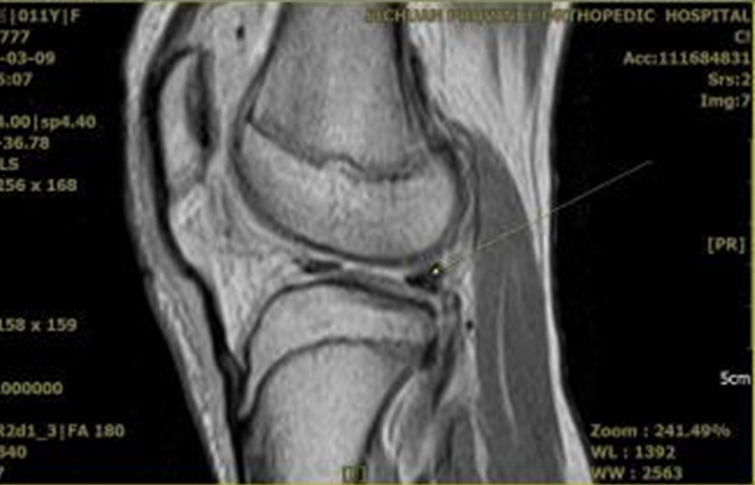

术前在显示前叉韧带全长的MRI矢状位上,按照预置内、外排锚钉之直径、长度和击入方向,规划生长板上内固定物所占空间尺度,如图8所示。内排钉选择直径3.0mm,长度10.8mm可吸收锚钉,内置双色半可吸收2号骨科高强缝线(Gryphon BR);外排钉选择直径4.75mm,长度17.8mm可吸收锚钉(Healix Advance BR Knotless)。

图8 术前MRI上规划胫骨生长板上内、外排锚钉置入之空间尺度